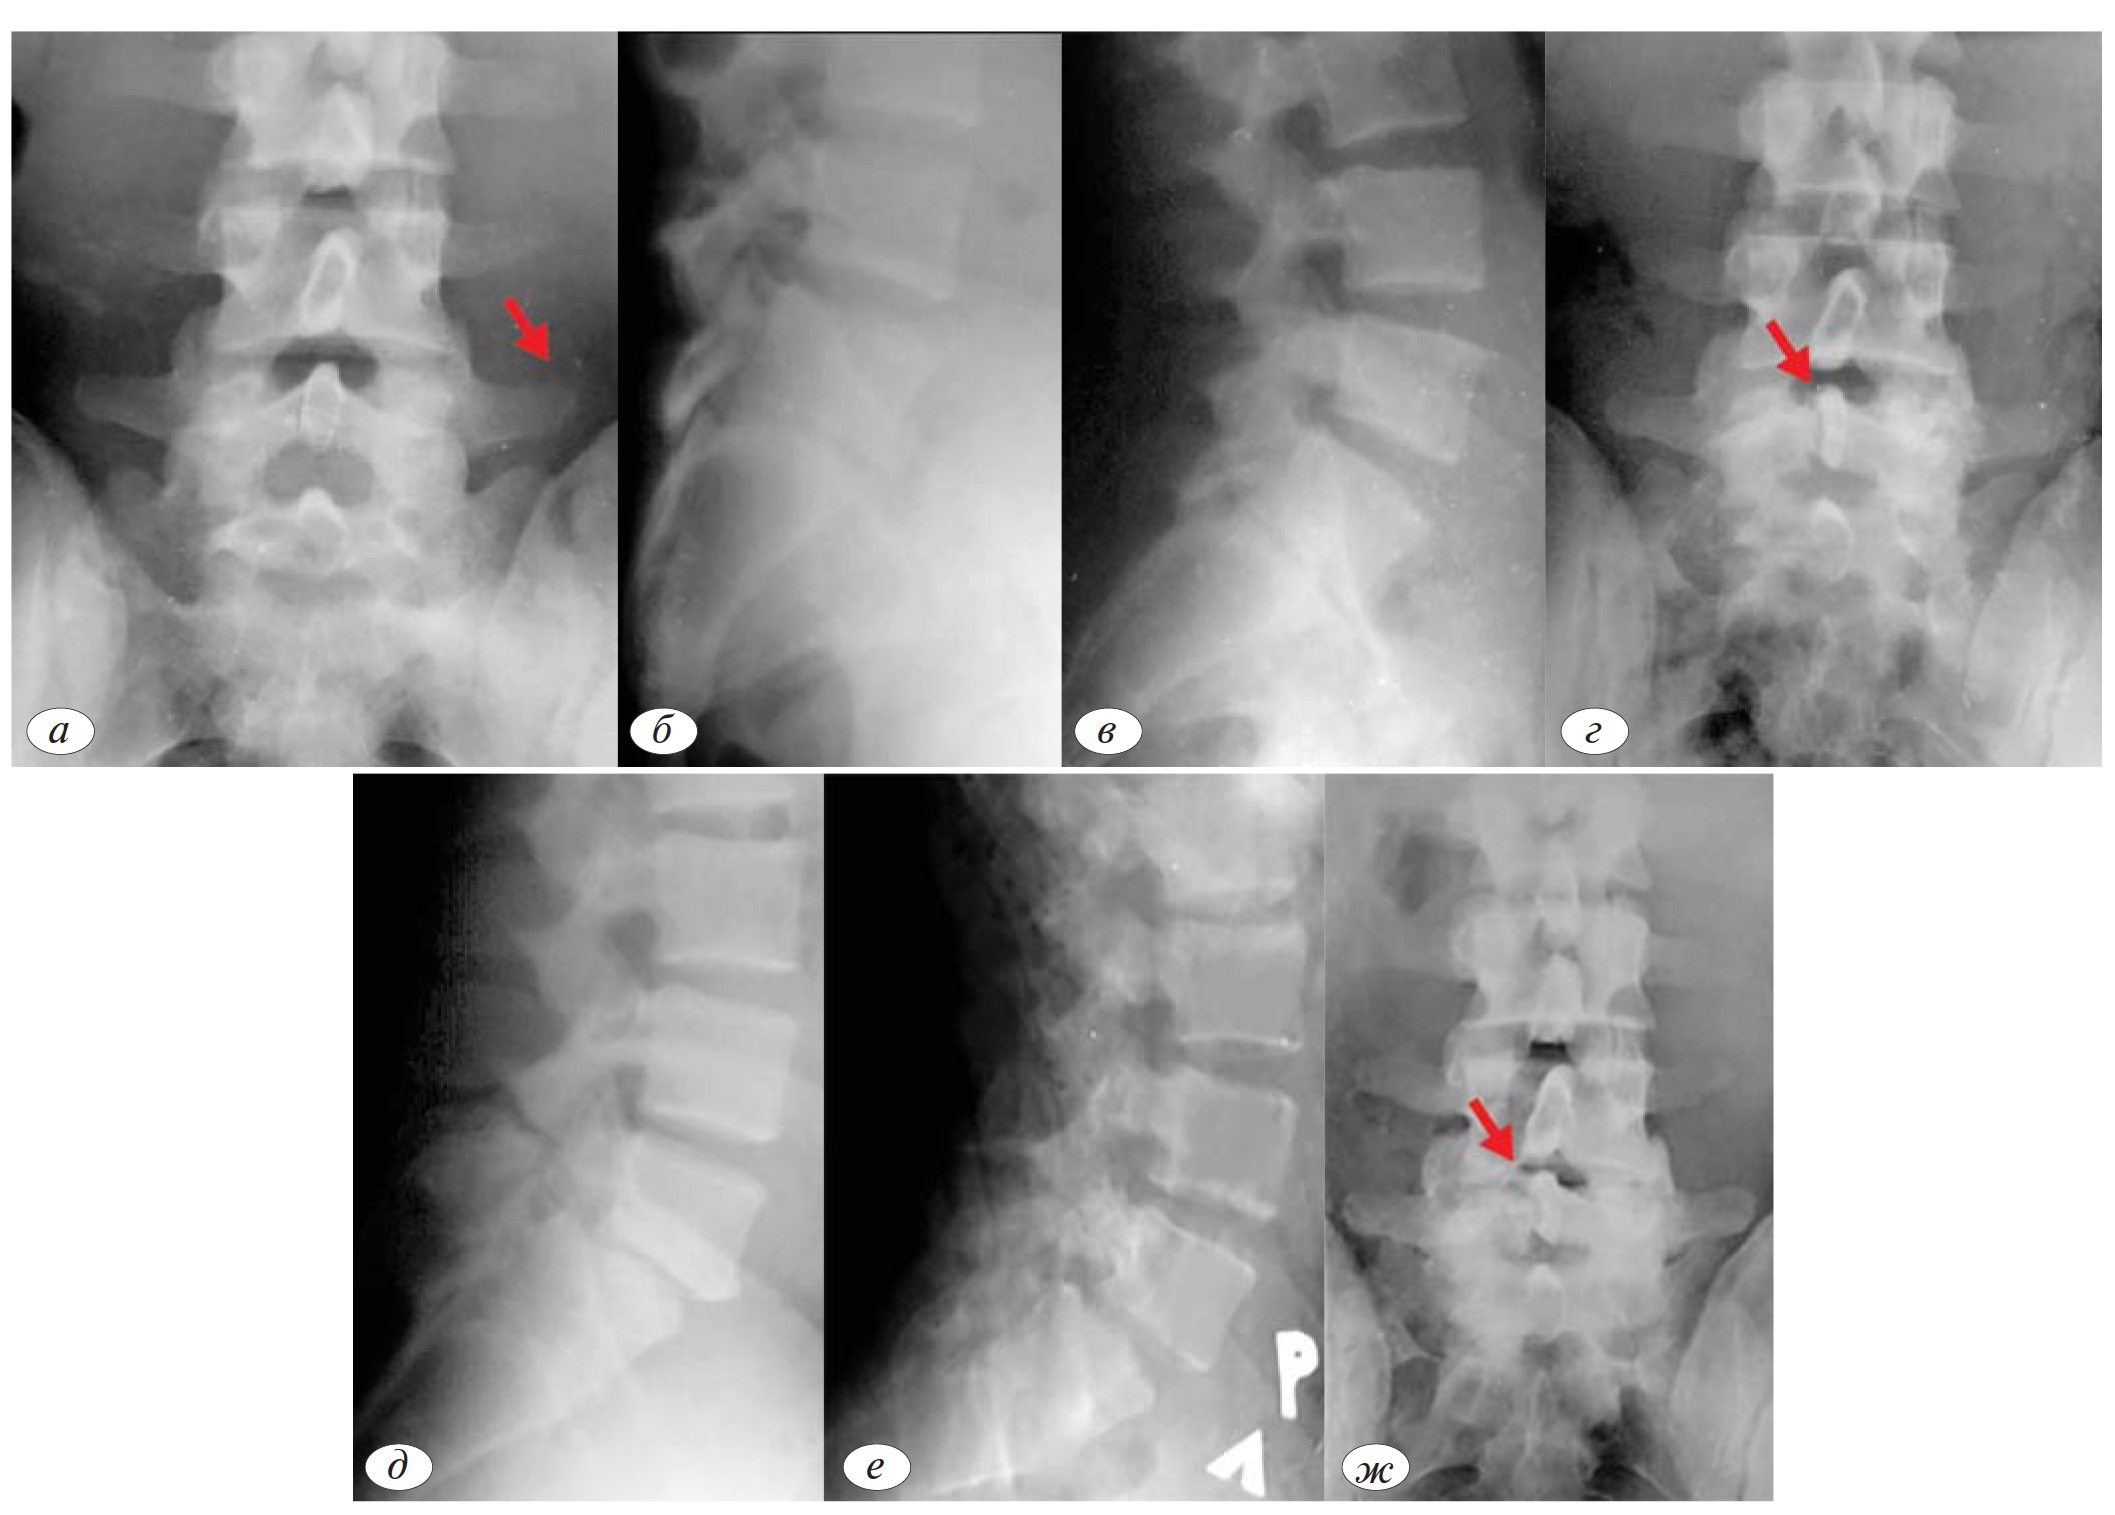

В качестве примера может служить развитие заболевания у больного М., 22 г., солиста балета. Боли в поясничном отделе позвоночника возникли в момент приземления при выполнении прыжков с максимальным разгибанием позвоночника и нижней конечности. После кратковременного консервативного лечения вновь приступил к работе. Через 6 мес в связи с выраженным болевым синдромом обратился в клинику спортивной и балетной травмы ЦИТО, где при рентгенологическом обследовании выявлен спондилолиз позвонка L4 с явлениями нестабильности. При биохимическом исследовании — кальций крови — 2,1 ммоль/л, ЩФ 92 Е/л; кальций мочи 8,2 ммоль/сут. Интенсивность болевого синдрома — 15 баллов. Лечение: ортопедический пояс на 7 дней, НПВП на 5 дней. В остром периоде выполнены 3 инъекции озоно-кислородной смеси в паравертебральные мышцы с двухдневным интервалом. лечебная гимна

стика, направленная на ликвидацию мышечного дисбаланса, 3 курса укрепляющего массажа мышц спины и брюшной стенки по 20 процедур, электростимуляция мышц до 15 процедур, получал Альфа-Г),Тева 0,75 мг ежедневно в течение 12 мес и препараты кальция в суточной дозе 500 мг, сосудистые препараты, витамина группы В. На контрольной рентгенографии, выполненной через 6 мес, отмечено почти полное восстановление дефекта. Интенсивность болевого синдрома к этому времени снизилась до 3 баллов. Больному разрешена профессиональная деятельность (рис. 1 а—ж).

Рис. 1. Больной М., 22 г, солист балета. а — подобный прыжок — «пусковой механизм» спондилолиза; б, в — через 6 мес после возникновения болевого синдрома — спондилолиз L4 позвонка, нестабильность; г, д — рентгенограммы в 3/4 — двусторонний спондилолиз L4 позвонка; е, ж — ФРИ через 6 мес после начала лечения, частичная регенерация дуги позвонка L4, возобновление профессиональной деятельности.